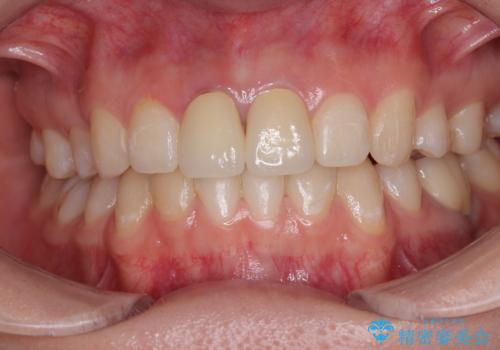

神経を取って変色した歯 オールセラミッククラウンで綺麗に仕上げる

明るく自然な口元になりました。